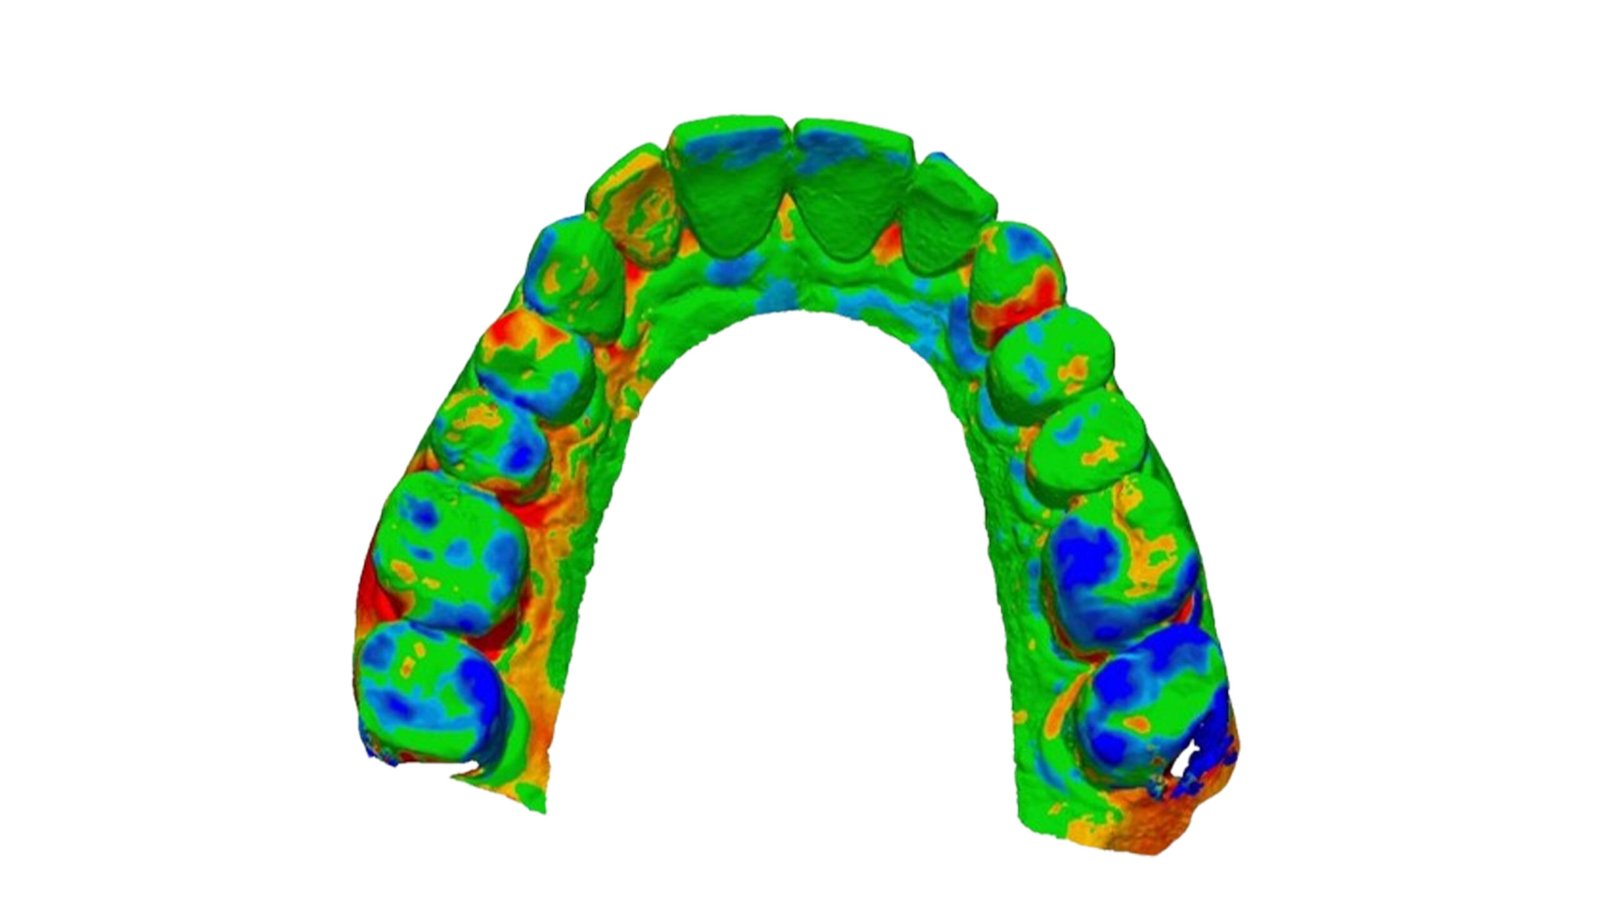

This section specializes in high-precision 3D deviation mapping to compare pre- and post-treatment anatomical or implant-related geometries. Using advanced superimposition and deviation algorithms, we quantify micro-level shifts, deformation zones, and structural discrepancies with sub-millimeter accuracy. These analyses support quality control, surgical verification, and design validation. The resulting deviation heat-maps provide clear, data-driven insights that enhance clinical decision-making and device optimization.